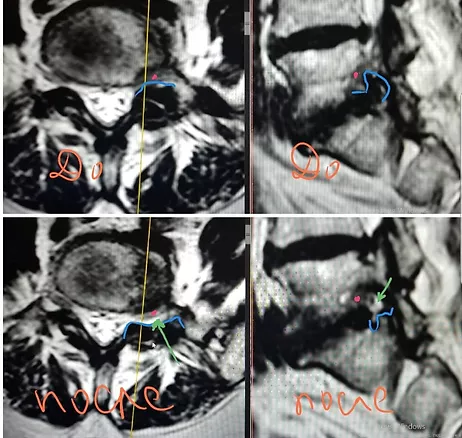

МРТ до и после операции - эндоскопической фораминотомии при фораминальном стенозе на уровне L5-S1. Красная точка это корешок. Синими границами показаны костно-связочные структуры, которые давят на корешок до операции. Зеленая стрелка показывает свободное пространство для корешка - белого цвета, освободившееся после операции.